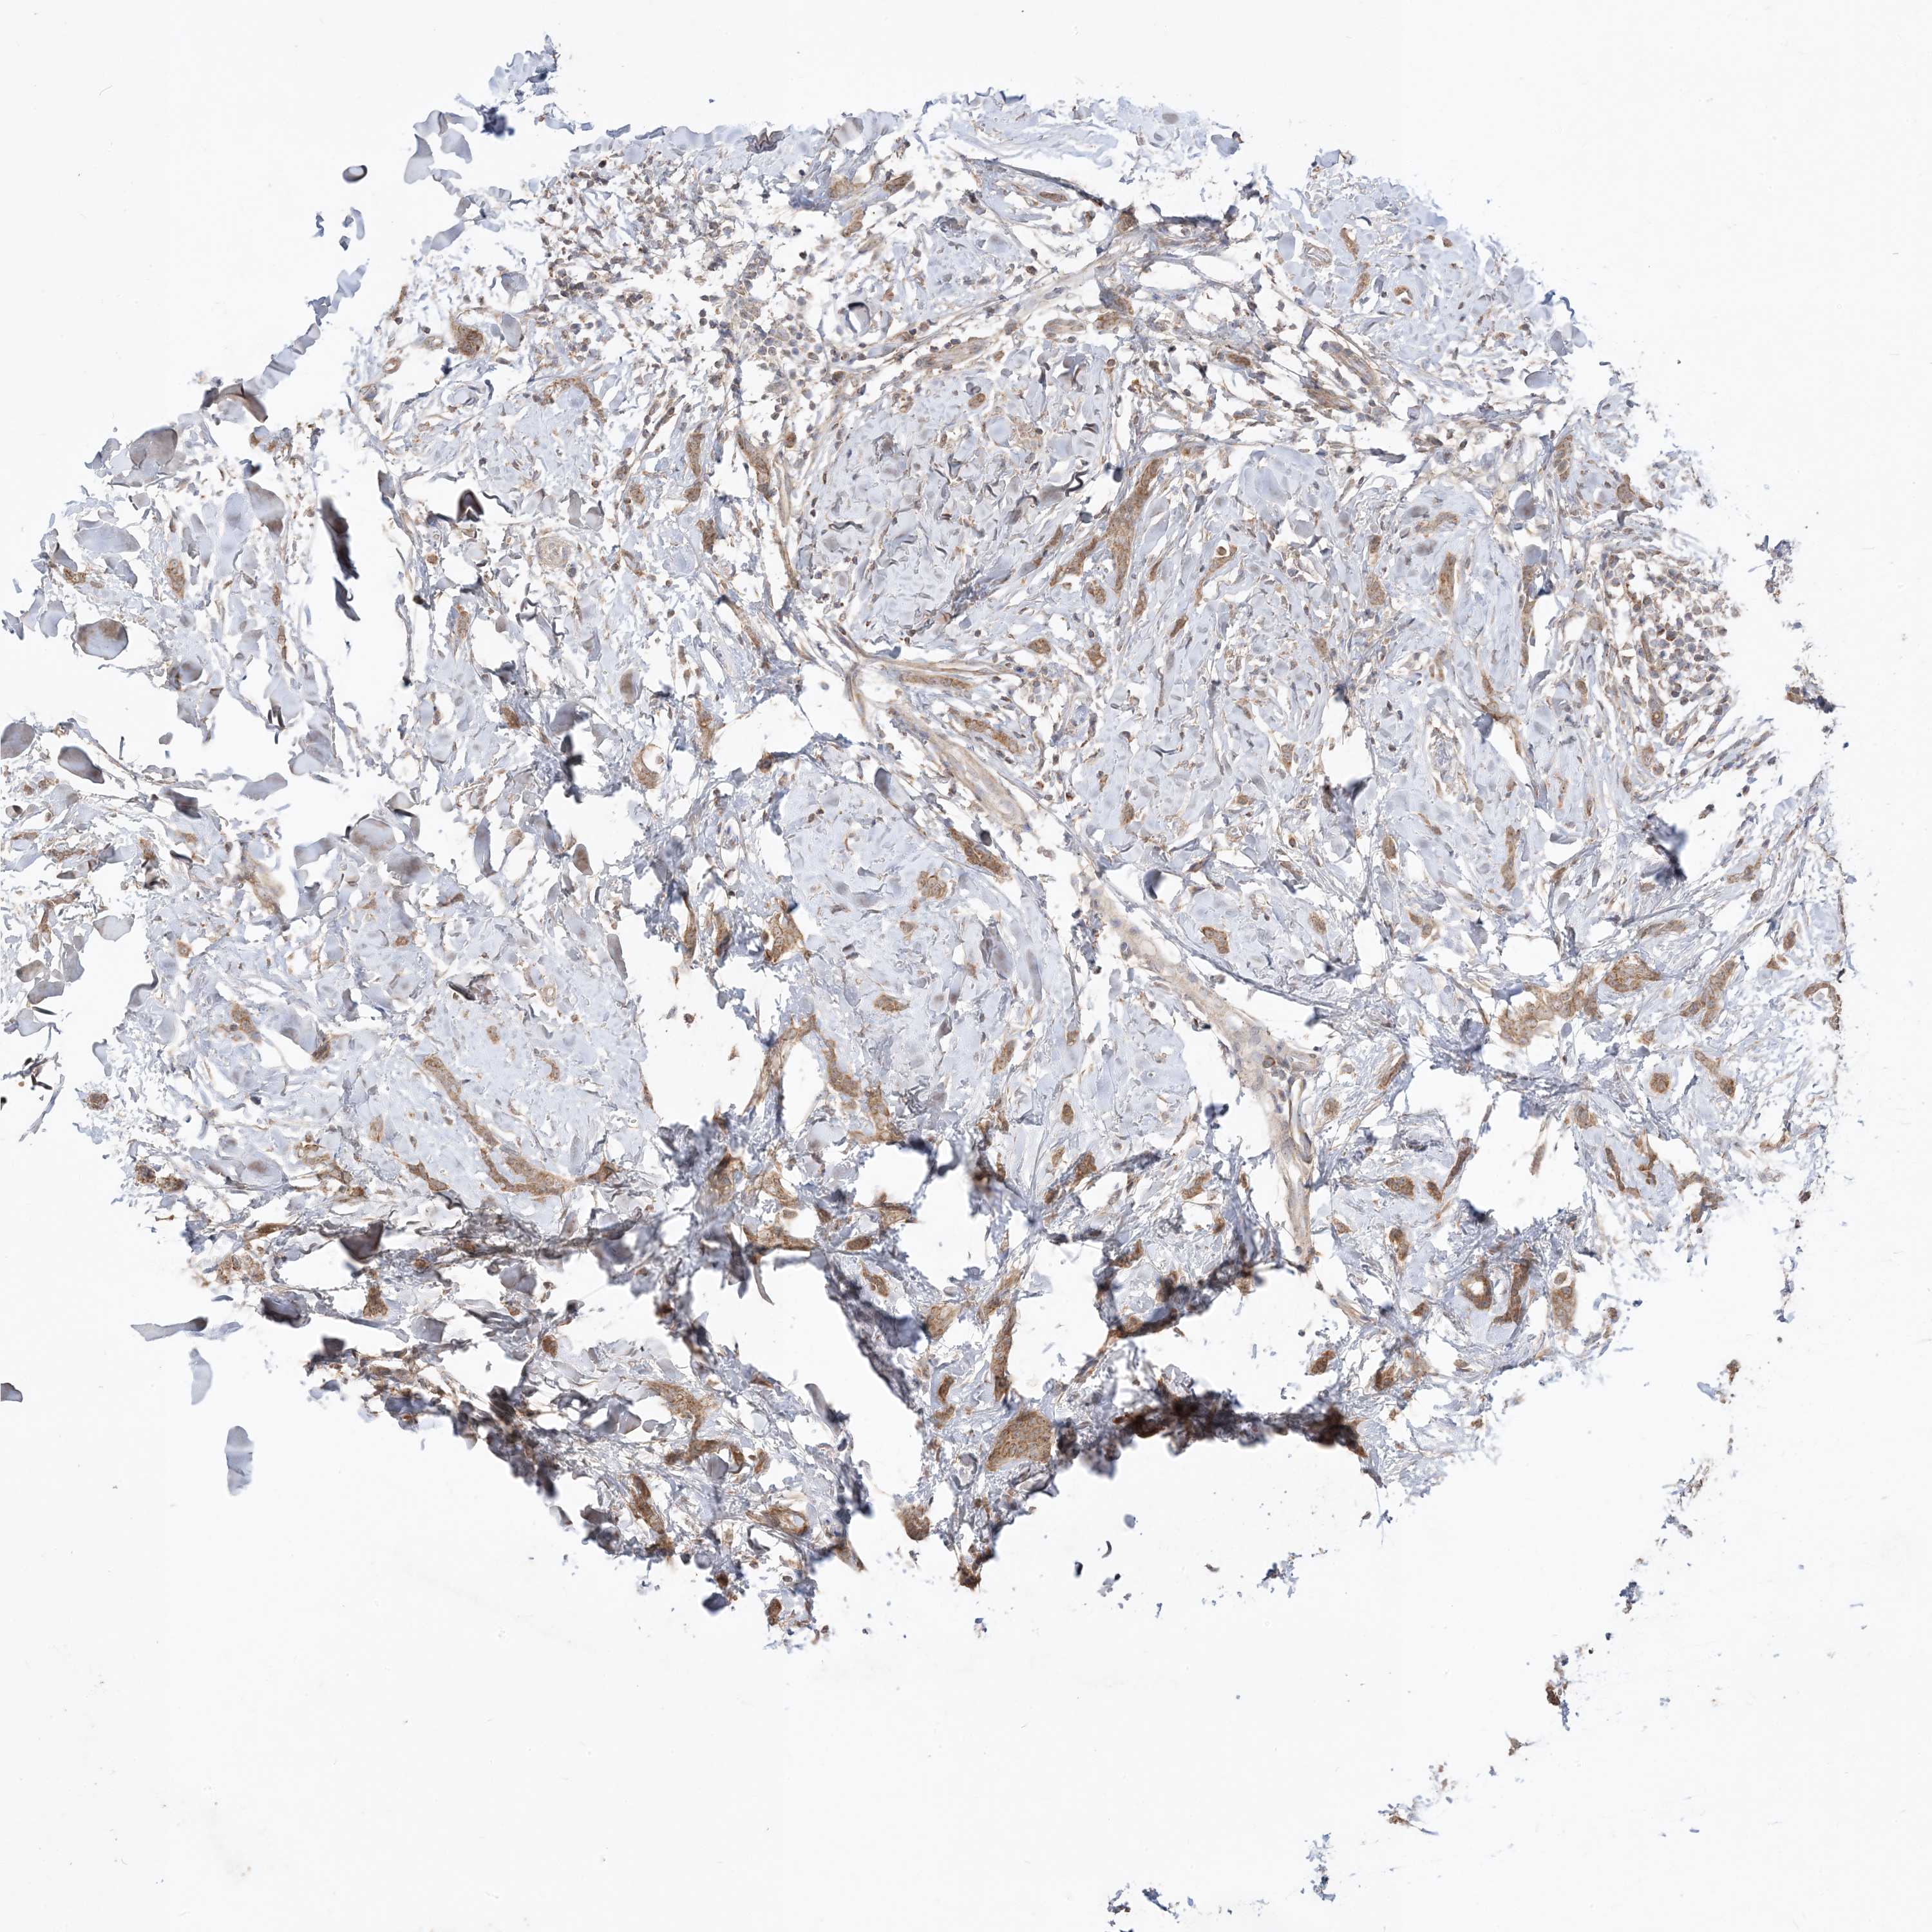

CANCER BREAST CANCER Show tissue menu

BRCA TCGA BRCA VALIDATION PROTEIN EXPRESSION